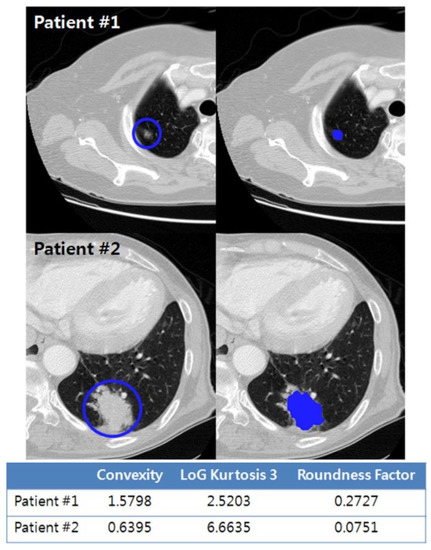

| Convexity | 0.004 | 0.078 | 0.013–0.447 | |

| LoG Kurtosis 3 | 0.034 | 1.085 | 1.006–1.170 | |

| Roundness factor | 0.009 | 2.384 | 1.246–4.561 |